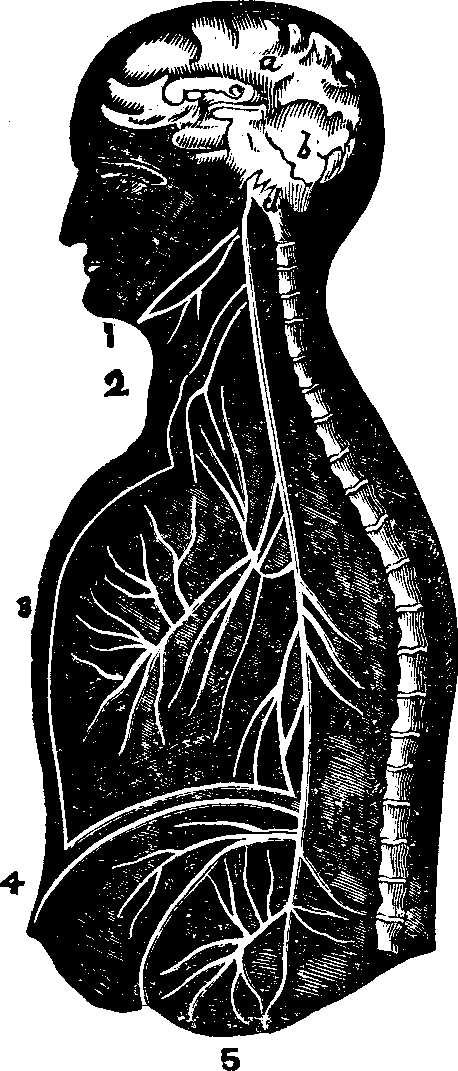

substance, and the arrangement of the pigmentary matter. C.

Transverse sections, showing the distinction between the cortical and

medullary substances, and the central collection of pigmentary matter,

sometimes found in the latter. Magnified 310 diameters.

Hairs are horny appendages of the skin, and, with the exception

of the hands, the soles of the feet, the backs of the fingers and toes,

between the last joint and the nail, and the upper eyelids, are distributed

more or less abundantly over every part of the surface of the body. Over